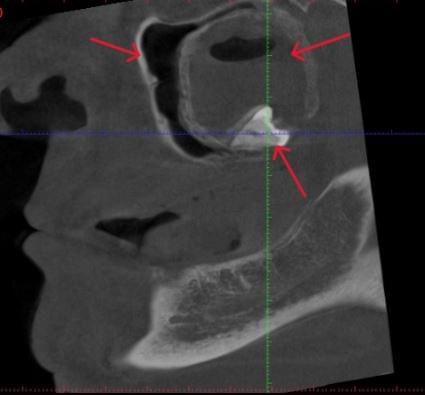

Діагностика гайморових пазух за допомогою КТ

У сучасній медицині КТ придаткових пазух носа (або КТ синусів) — це «золотий стандарт»

діагностики для ЛОР-лікарів та щелепно-лицевих хірургів. Звичайний рентген часто не

показує повну картину, а МРТ не завжди доступний і дорожчий. Комп’ютерна томографія дає

детальну 3D-модель усіх пазух (гайморових, лобних, клиновидних та решітчастого

лабіринту) за 10 секунд і з мінімальною дозою опромінення.

КПКТ (конусно-променева комп’ютерна томографія) — це 3D-знімок високої роздільної здатності. На відміну від звичайного рентгену, КТ показує: